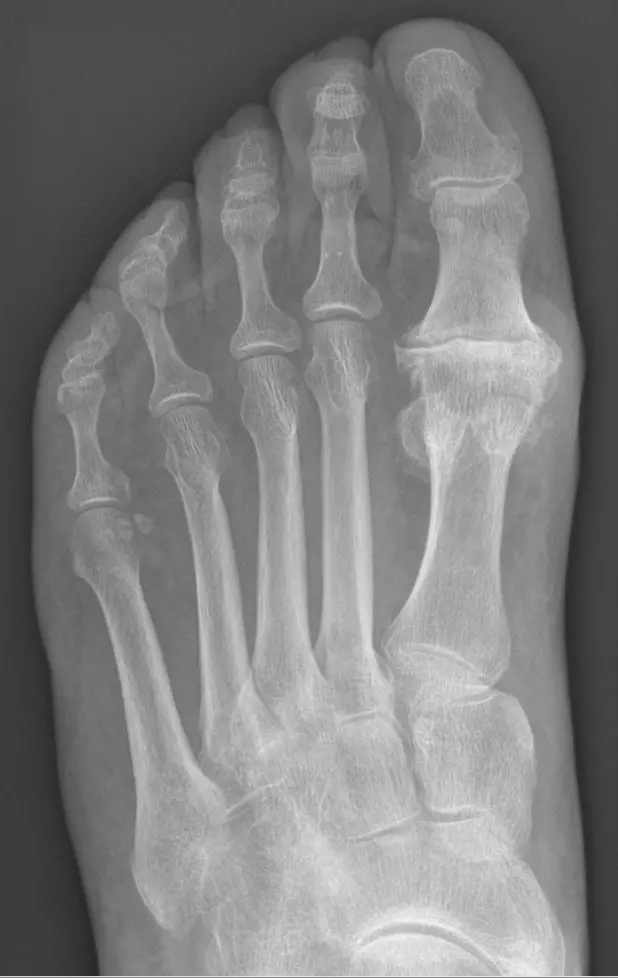

Hallux Valgus is the medial deviation of the first metatarsal, lateral deviation of the hallux and prominence of the first metatarsal head. It is commonly referred to as a ‘Bunion’. This condition is most common in middle aged females and is caused by abnormal mechanics of over-pronated feet (meaning more weight is transmitted through the medial side of the foot than the lateral side). This is the most common foot deformity.

Image - Hallux Valgus

Creative commons source by Lamiot [CC BY-SA 4.0 (https://creativecommons.org/licenses/by-sa/4.0)]